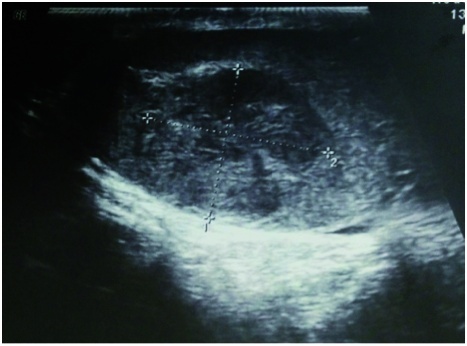

Generell erfolgte wie bei allen männlichen Patienten zusätzlich eine Palpation des äußeren Genitale. Hierbei zeigte sich eine von Seiten des Patienten bisher unbemerkt gebliebene kirschgroße Induration im Bereich des linken Hodens. Die nachfolgende Hodensonographie mit einem 7,5 MHz-Schallkopf erhärtete den Verdacht auf einen etwa 2 cm im Durchmesser messenden Tumor des linken Hodens (Abbildung); im rechten Hoden wurde eine Mikrolithiasis nachgewiesen. Die initial laborchemisch bestimmten Tumormarker AFP, ß-HCG und LDH waren normwertig.